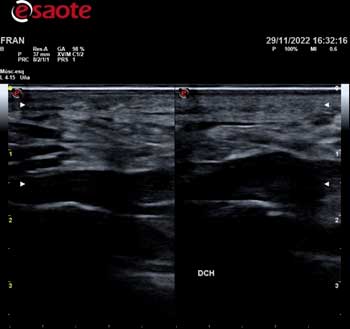

La utilización de un ecógrafo para diagnosticar la fasciosis plantar es esencial y es la herramienta más idónea para su examen.

En ecografía observamos una señal hipoecoica con separación de las fibras de la fascia plantar. El valor normal de fascia plantar sana es de 3mm. Es importante realizar un estudio ecográfico comparativo en el otro pie para visualizar el rango de grosor de la otra fascia.

A continuación adjunto varios casos de imágenes ecográficas con fasciopatía plantar: